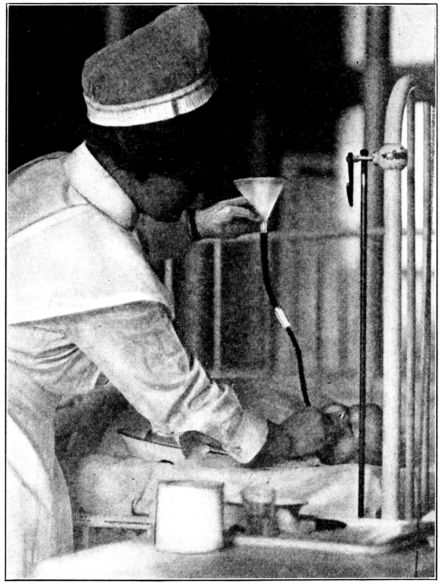

| 168. | Preparing the baby’s milk | 493 |

| 181. | Gavage | 524 |